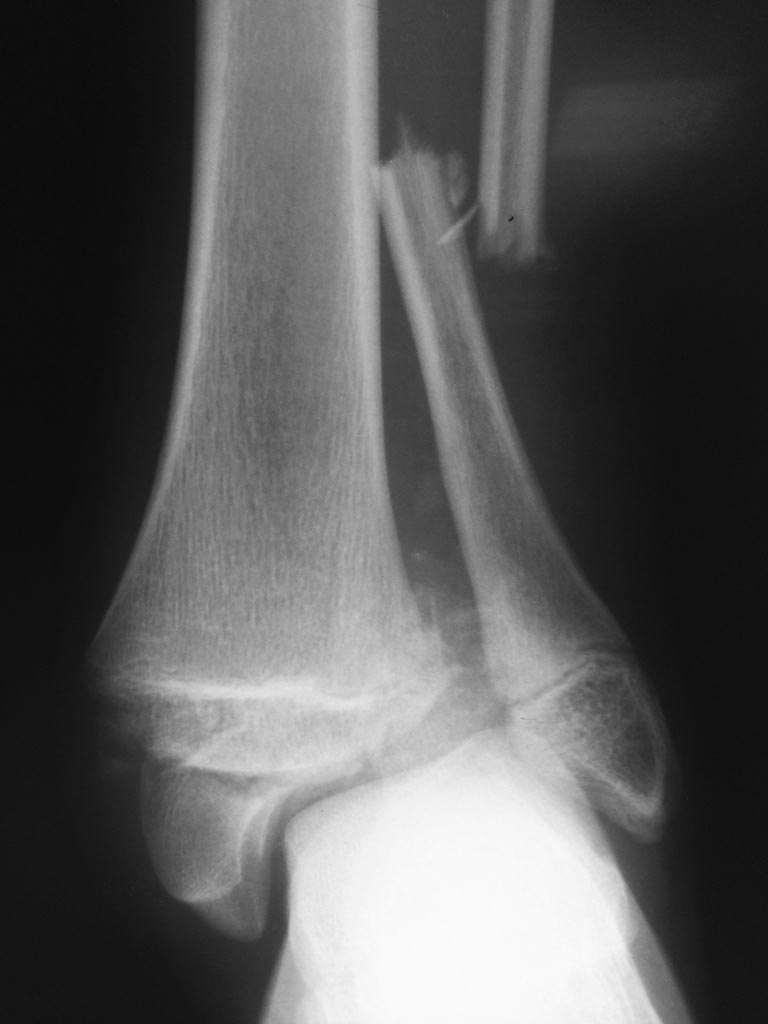

закономерная смена его на вытяжение в связи с появлением фликтен.

Имя     : 3 на вытяжении.JPG

Тип     : image/jpeg

Размер  : 51931 байтов